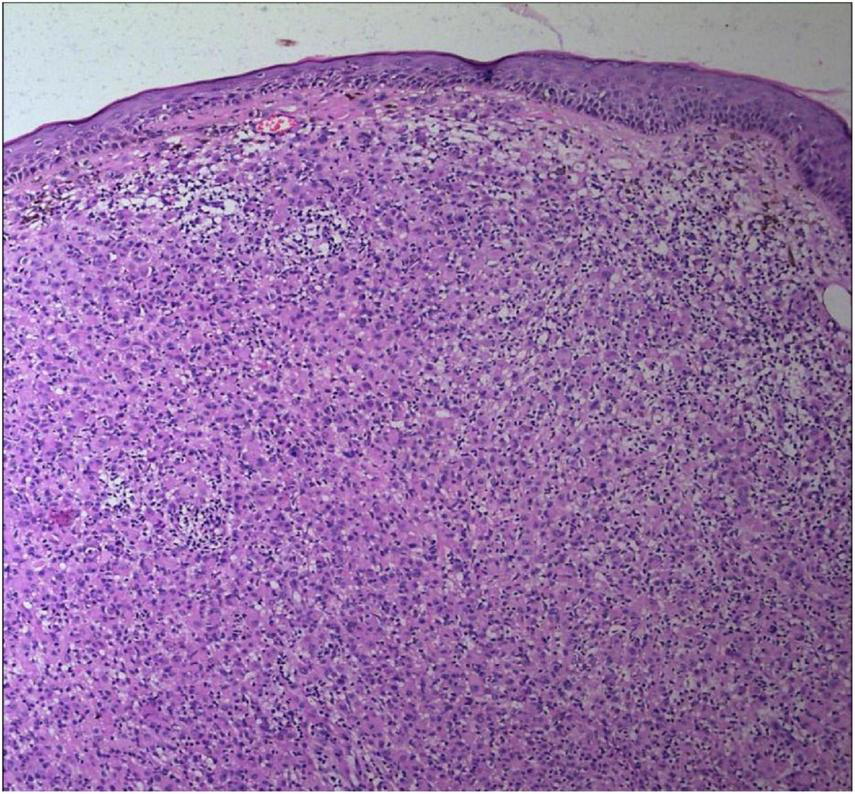

FIGURE 2

The epidermal processes disappeared, and the dermis was diffusely infiltrated by substantial tumor cells that were in the nested or clumpy form (Hematoxylin and Eosin Stain, × 100).

No abnormalities were found upon routine blood and urine tests, coagulation function test and syphilis/HIV screening. Chest X-ray and abdominal B-ultrasound also revealed no abnormalities. Cutaneous histopathology: epidermal processes disappeared, and the dermis was diffusely infiltrated by substantial tumor cells that were in the nested or clumpy form. These polygonal tumor cells were round or oval, which had abundant cytoplasm filled with eosinophilic granules, and were stained pale pink. The cellular nuclei were small, hyperchromatic and centered, with few mitotic figures, and multiple nuclei were observed in some tumor cells. Immunohistochemistry: S-100 (+), CD56 (−), NSE (−), vimentin (+), CD68 (+), Ki-67 (+), cell proportion: 5%, p53 (−), SAM (+−). CK (−), calponin (−), CD163 (−), desmin (−), CD34 (−), CD45 (−), CD30 (−), SMA (1A4) (−), ALK (−), HMB45 (−), melan-A (−).

The dermis was diffusely infiltrated by substantial tumor cells that were in the nested or clumpy form. These polygonal tumor cells were round or oval, which had abundant cytoplasm filled with eosinophilic granules.